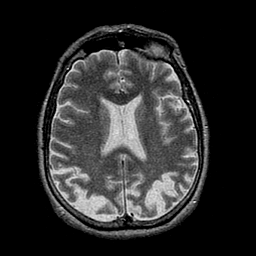

Alzheimer's disease: overlay -- Slice #32

[Home][Help][Clinical] Slice 32